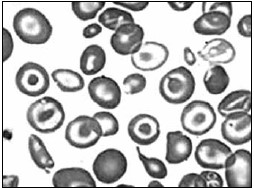

Foi realizado o esfregaço sanguíneo para confirmação do laudo. Assinale a alternativa que apresenta a descrição das células sinalizadas a seguir e a patologia a qual correspondem.

Figura 2

(Laudo e imagem cedidos pelo Laboratório de Análises Clínicas do Centro Universitário FMABC)

Foi solicitada uma curva de fragilidade osmótica a uma criança de 2 anos de idade, após a mãe descrever ao médico generalista a dificuldade de seu filho ter boa qualidade de vida devido às suas repetidas internações, quadros de infecções e anemia, sem sucesso após terapia com ferro. O esfregaço sanguíneo revelou poiquilocitose com presença de hemácias em alvo, hipocromia e anisocitose. Avaliando a curva de fragilidade osmótica, sugere-se um quadro de:

Figura 1